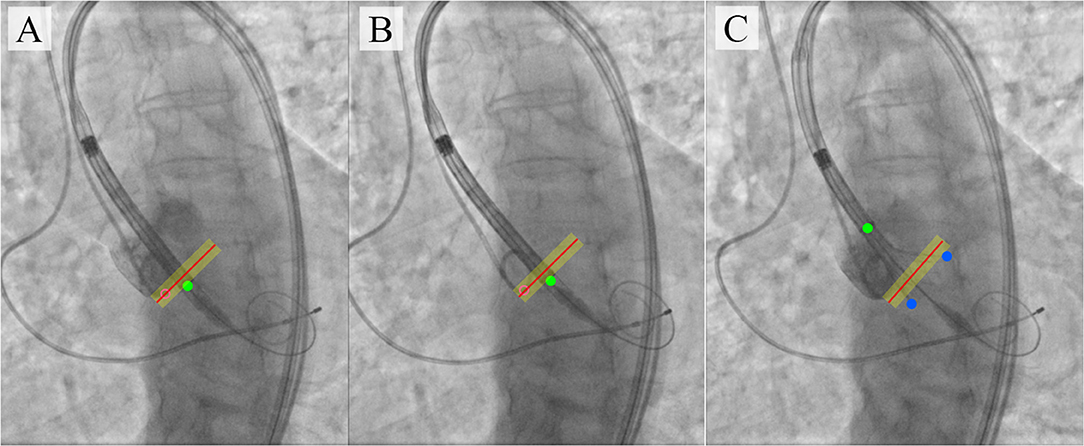

Предложенное алгоритмом место установки искусственного аортального клапана. Источник: Danilov et al. / Front. Cardiovasc. Med., 2021.

Для обучения алгоритма ученые исследовали и разметили несколько десятков видеозаписей процесса имплантации искусственного клапана в аорту, в результате чего получилось около 3,5 тыс. снимков. Анализируя эти фотографии, программа должна была определить положение 11 ключевых точек на поверхности сосуда, клапана и системы его установки внутрь аорты.

Проверив результат обучения на неразмеченных снимках аорты, ученые выяснили, что в 95% случаев алгоритм определял положение этих точек корректно. При этом он мог выявлять их в режиме реального времени, что позволяет использовать подобные нейросети прямо при проведении операции по имплантации клапана. По словам Овчаренко, ученые разрабатывают новые версии алгоритма, которые будут адаптированы для работы с разными моделями клапанов.